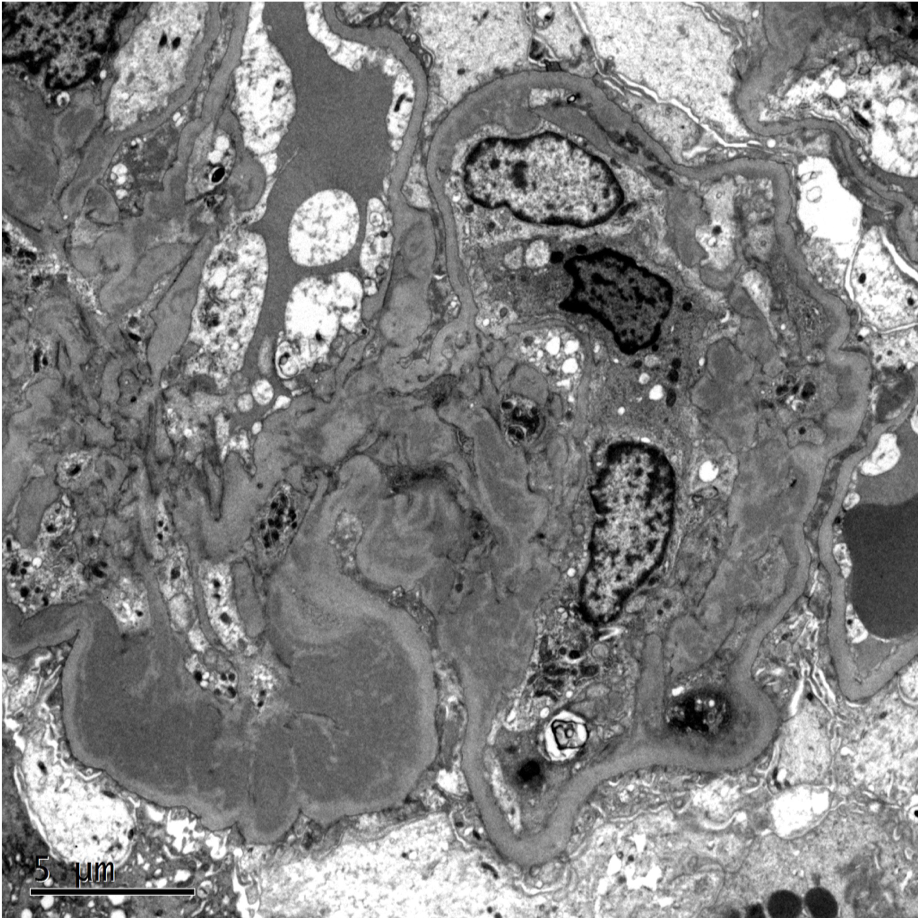

Kidney Biopsy Near Me. the department sees a wide range of renal disorders, from the early phases of renal disease to patients newly presenting with. some patients may eventually need a kidney biopsy to distinguish the kind of kidney disease that they have, as well as to assess the eventual renal. some patients may eventually need a kidney biopsy to distinguish the type of kidney disease and evaluate the eventual kidney. renal biopsy is a procedure whereby a special needle is passed through the skin near the loin area at the back to obtain. the renal laboratory provides clinical support for the performance and processing of kidney tissues for biopsy and. a kidney biopsy is a critical procedure that allows us to diagnose the specific nature of your kidney condition. renal biopsies are subjected to examination by light microscopy, electron microscopy and immunofluorescence.